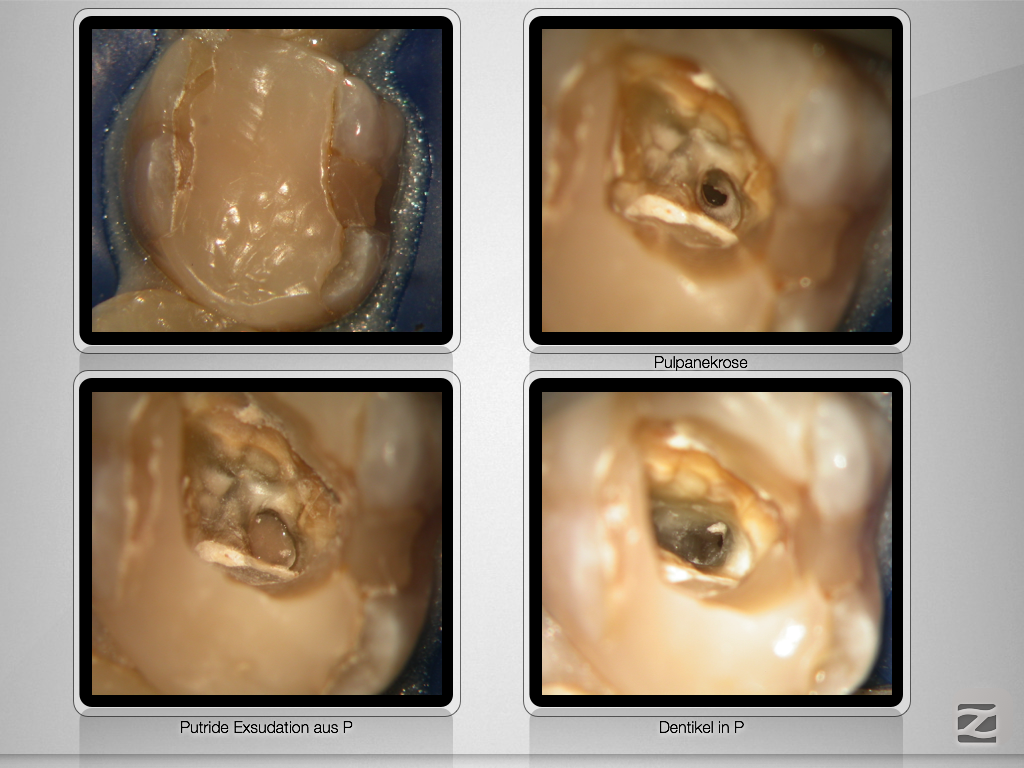

Navigierte Aufbereitung